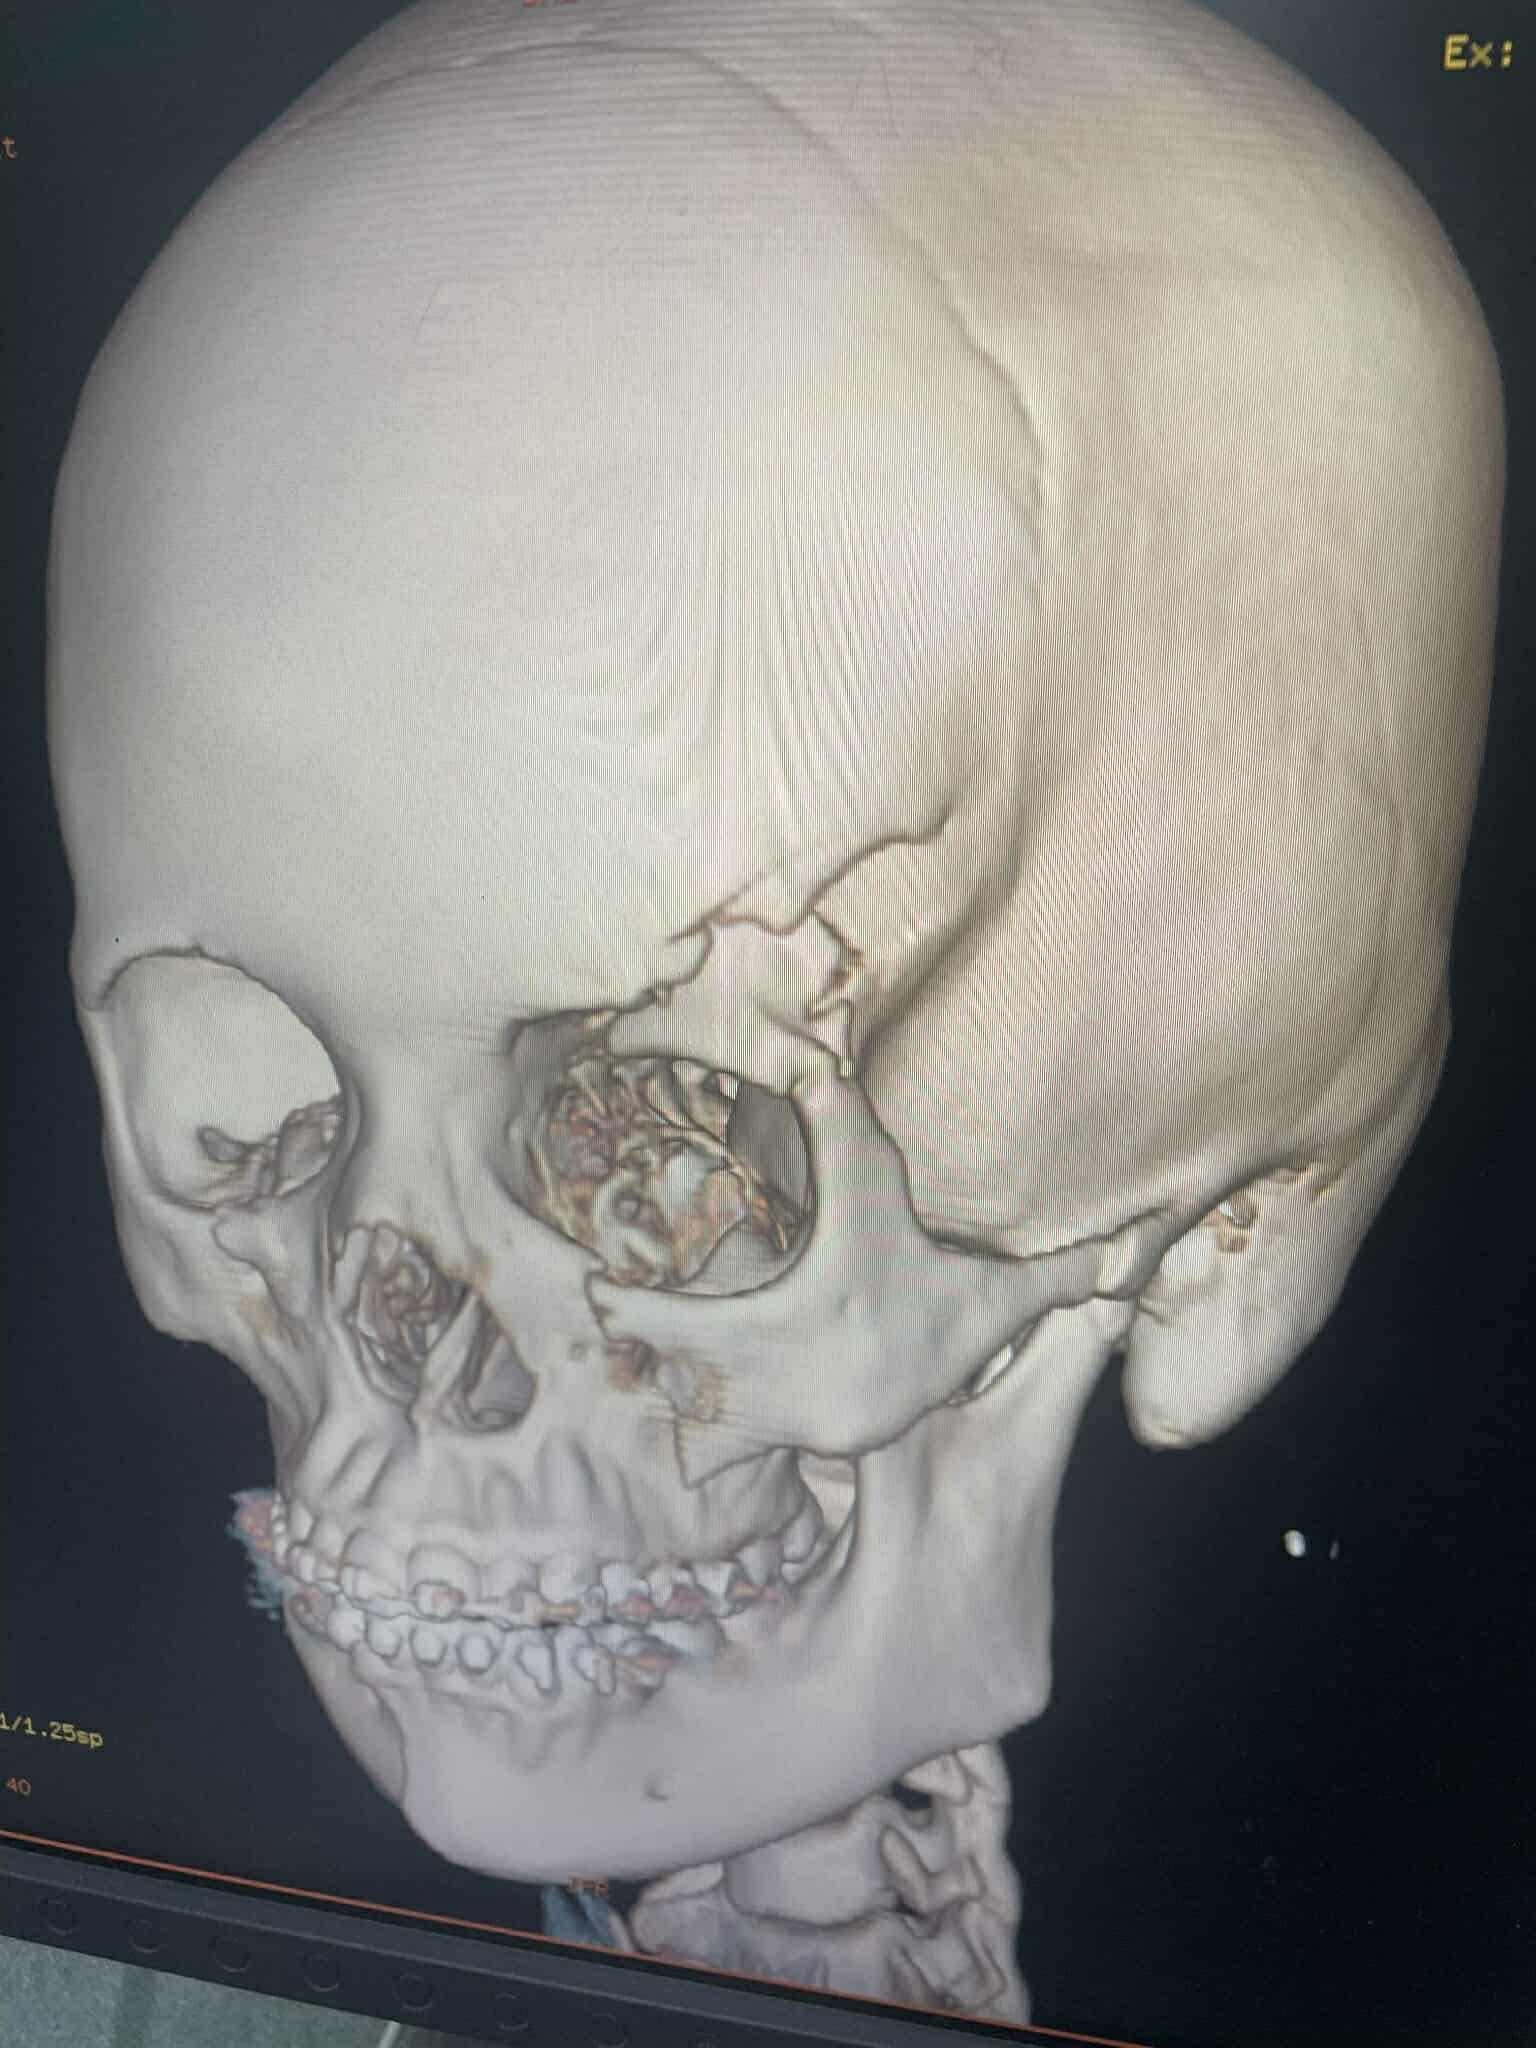

Elsa was severely injured. She now suffers from:

A fractured skull

A fractured chin

A fractured arm

Vision loss in her left eye (due to the skull fracture)